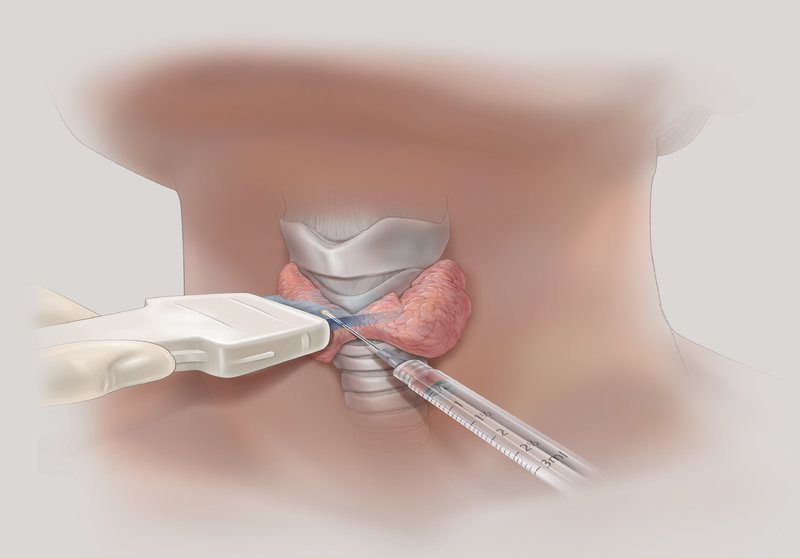

Остеосцинтиргафия позволяет оценить наличие/отсутствие метастатического поражения костей скелета. Тонкоигольная аспирационная биопсия выполняется преимущественно под контролем УЗИ, позволяет прицельно получить материал для цитологического исследования, что позволяет в большинстве случаев верифицировать диагноз. ТАБ подозрительных лимфатических узлов дает возможность установить метастатический характер поражения.